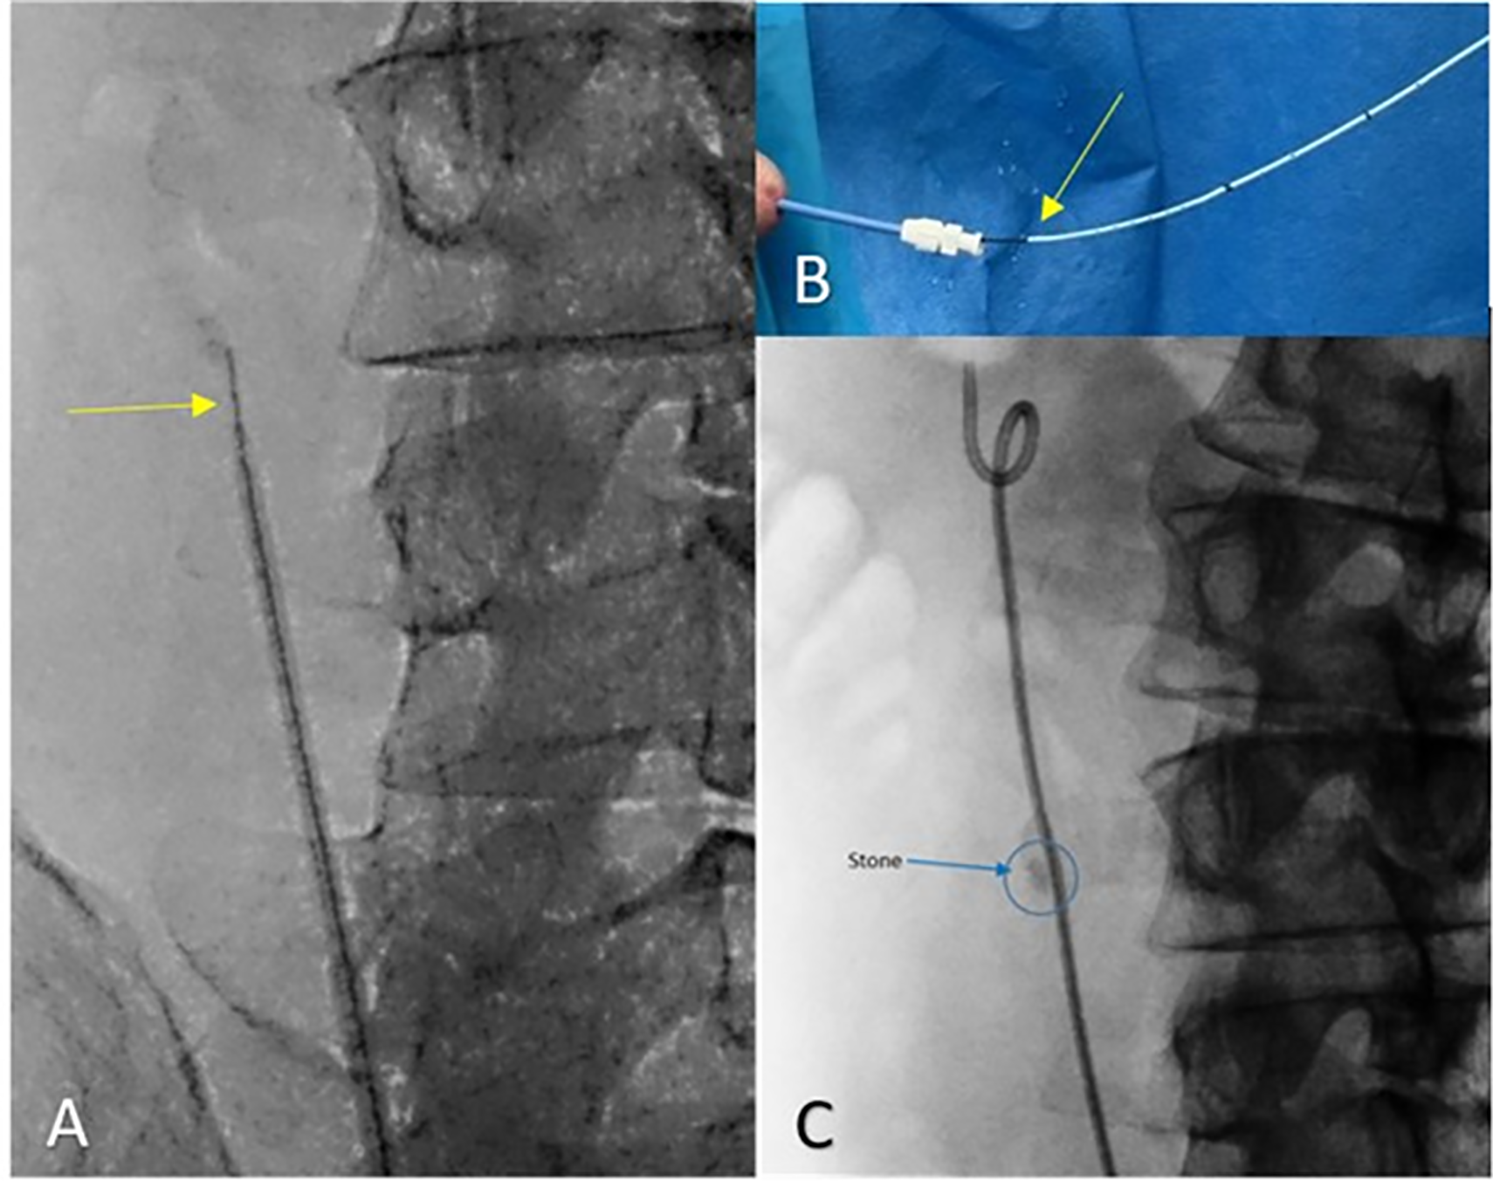

We have included a sample demonstrative case of a 7 mm right ureteral stone, as can be seen in Figure 2. The stone was not amenable to the standard retrograde stenting approach, since after passing a guidewire alongside the stone, the degree of ureteral occlusion prevented the safe passage of a double-J stent. A ureteral dilator was positioned close to the stone tip as described above and shown in Figure 3A,B, followed by passage of a double-J stent through the ureteral dilator sheath as seen in Figure 3C.

FIGURE 3. Sequential stages of double-j stent placement over a guidewire using an 8/10 Dilator (A) The ureteral 8/10 dilator is advanced on the guidewire (yellow arrow) and positioned close to the stone. (B) Double-J stent (yellow arrow) advanced through the dilator sheath. (C) Double-J stent in place